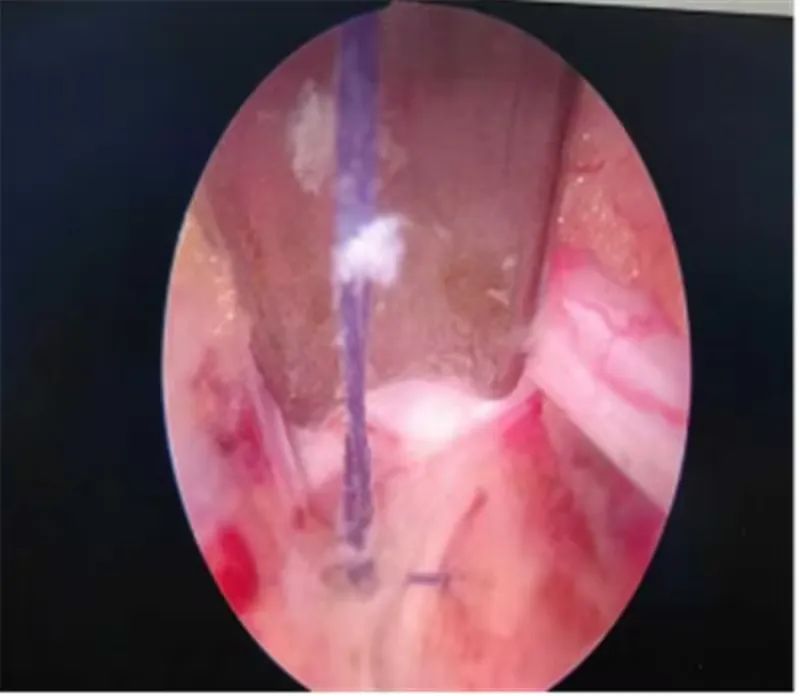

近日,榆林市星元医院成功开展了市首例关节镜辅助单孔脊柱手术下黄韧带悬吊、保留、纤维环缝合术(Arthroscopic-assisted Uni-portal Spinal Surgery 以下简称AUSS),在为患者成功解决病痛的同时,通过对椎板减压、椎间盘切除、纤维环缝合处理,为患者术后下肢疼痛及功能的恢复提供帮助,脊柱微创技术领域再次实现新突破。随后接连开展多例相同手术,术后这些患者均获得了令人满意的治疗效果。该技术的成功开展,标志着我院微创外科在脊柱微创领域又迈上了新的台阶。

37岁的辛某某,腰臀部酸胀1年,左下肢放射性疼痛1月,曾在当地医院诊断为腰椎间盘突出症给予理疗、射频消融等治疗后症状缓解不明显,近1月来出现左下肢放射性疼痛,从臀部放射至大腿后侧、膝关节、小腿外侧,疼痛进一步加重,严重影响到患者的日常生活。不能下地活动,为寻求进一步治疗,来到市星元医院就诊。经过专科查体及影像学辅助检查,患者被诊断为腰椎间盘突出症、腰椎管狭窄症。邢永军主任医师团队综合评估患者病情,结合患者年龄、椎管狭窄程度、椎间盘退变程度、椎间隙高度等各项指标,经与患者充分沟通,开放手术创伤太大,单轴内镜受灵活性所限,不一定能够达到手术目的,“AUSS是传统脊柱手术内镜化方案,兼具开放手术和内镜手术的优势,且创伤比双通道的UBE手术更小,是目前最好的选择!,制定了“AUSS关节镜辅助单孔脊柱手术”的治疗方案。术中,医生通过可视化内镜辅助对患者狭窄的椎管进行减压、突出椎间盘进行摘除,对破裂的纤维环进行缝合,提高患者术后生活质量,术后患者恢复良好。下肢放射性疼痛完全消失。

AUSS技术即关节镜辅助单切口脊柱手术,是目前新兴的脊柱内镜技术,结合了UBE技术与孔镜技术的优点,是单轴内镜技术的延续、UBE双通道技术的改进、开放手术内镜化的体现,是将工作通道与观察通道置于同一软性切口内,具有减压范围广、操作空间大、定位简单、透视少等特点,30度关节镜,视野范围广,镜头360度自由转动,减少操作盲区;不同内镜技术的结合:关节镜的三角操作以及后路同轴内镜的同轴摆动、旋转,以及非同轴旋转技术。